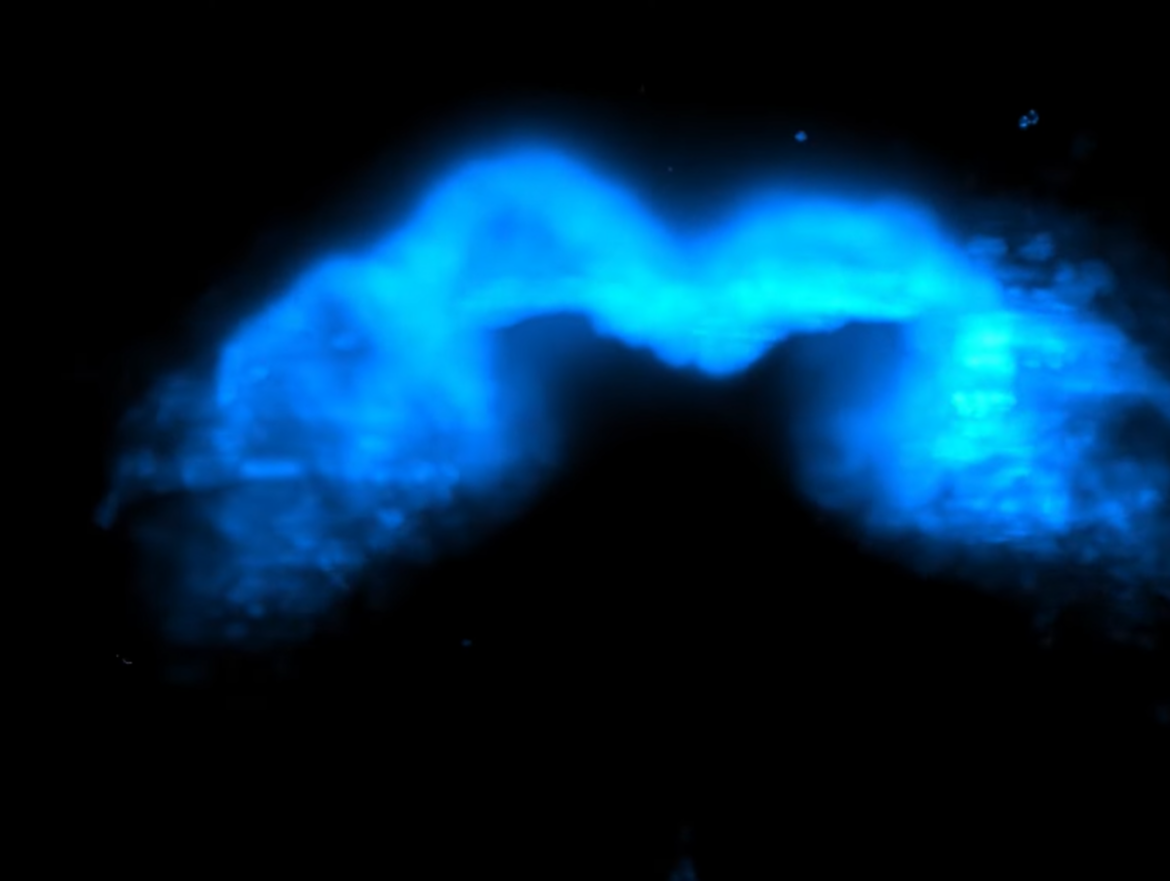

Στη συνέχεια, τα μυϊκά κύτταρα της καρδιάς συγκεντρώνoνται σε έναν μεγάλο σωλήνα που θα διαιρεθεί σε τμήματα για τη δημιουργία των τοιχωμάτων και κοιλοτήτων της καρδιάς. Σε περιπτώσεις μωρών με καρδιοπάθειες μπορεί να προκύψει μια τρύπα κατά τη διάρκεια αυτής της διαδικασίας. Χρησιμοποιώντας φθορίζοντες δείκτες, η ομάδα σημείωσε τα μυϊκά κύτταρα της καρδιάς (καρδιομυοκύτταρα), κάνοντάς τους να λάμπουν σε διαφορετικά χρώματα. Οι λήψεις πραγματοποιούνταν κάθε δύο λεπτά επί 40 ώρες και κατέγραψαν την κίνηση και διαίρεση των κυττάρων καθώς σχημάτιζαν ένα πρωτόγονο όργανο.

Αυτή η διαδικασία επέφερε σημαντικές γνώσεις σχετικά με την εμφάνιση των πρώτων κυττάρων που συμβάλλουν στη δημιουργία της καρδιάς στο έμβρυο.